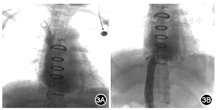

入院诊断为上下腔静脉梗阻,起搏导线植入状态。患者出现症状性上、下腔静脉梗阻,反复球囊扩张无效,病史长,经多学科会诊讨论及患者家属知情同意后行外科手术。胸骨正中开胸,充分游离右无名静脉、左无名静脉及上下腔静脉,同时游离一侧股静脉备用。肝素化后,于升主动脉插动脉管,股静脉插静脉管行下腔静脉引流,右无名静脉插管行上腔静脉引流,并行体外循环。右心房容积偏小,切开上腔静脉及部分左无名静脉,见起搏导线表面广泛内皮化,血管腔广泛偏细(图2A、2B)。切开下腔静脉近右心房入口处,见右心房壁组织呈环状增厚,内皮化的起搏导线卷曲成团,致使下腔静脉汇入心房处明显狭窄,去除内皮化的起搏导线,剪除增厚的心房组织,取自体心包,修剪合适大小心包组织加宽狭窄的下腔静脉、右心房、上腔静脉及部分左无名静脉(图2C);同时摘除起搏器,将起搏导线表面的纤维组织送病理检查。术后患者上下肢水肿明显好转,上下腔静脉CT提示加宽心包补片处血流通畅,上下腔静脉造影显示补片加宽处无狭窄(图3)。病理结果提示血管壁组织慢性炎性伴玻璃样及钙化病变。术后胸片提示较术前肺血流量增多。术后给予华法林抗凝[2~3 mg/次,1次/d,维持国际标准化比值(INR)2.0 左右],随访1个月,患者上下肢无水肿,一般情况良好。